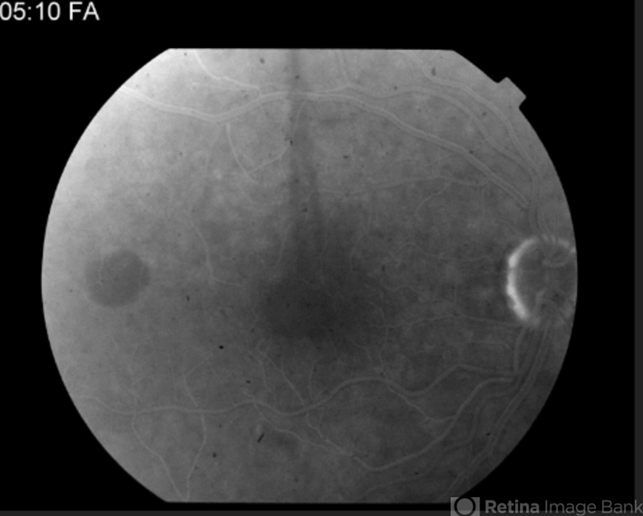

Multifocal Best Disease

Best disease, adult vitelliform dystrophy

Angiography reveals blocking defects due to pigment clumping with no evidence of CNVM.